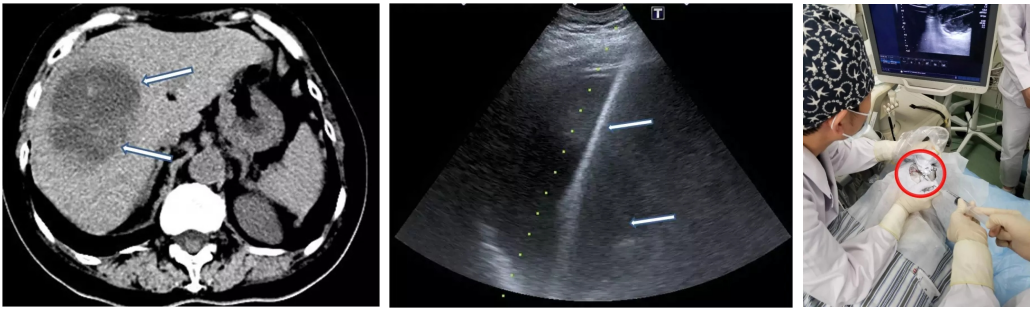

1月余前患者常规复诊,无明显呼吸道症状,复查胸部CT:右肺上叶新发结节灶。结合患者症状及影像学变化,做了充分评估,但是没有拿到有效的病原学证据,考虑真菌感染可能性大,后给予伏立康唑200mg bid口服治疗4周。

在此期间,抗真菌治疗2周复查胸部CT:结节空洞体积缩小,壁变薄。

在此期间胸部CT演变

住院期间(确诊血管炎),胸部CT未发现肺内有明显的浸润影。但是在治疗过程中,病人右肺上叶出现实性结节灶。本来要做肺穿刺,但在做肺穿刺之前发现肺内病灶出现一些变化,变成了一些像薄壁空洞、形态不规则的演变,当时担心会有出血的风险,就没有完成肺穿刺。于是继续让病人口服抗真菌药物治疗2周,抗真菌药物治疗之后,影像学发生了一些变化,由原来的实性结节变成薄壁圆形的空洞。

会不会有其他的表现能够验证血管炎复发这一点呢?通过气管镜的方法,还是通过肺穿刺活检更能够明确感染呢?我们选择了肺穿刺的方法,这是因为肺穿刺获得的病理既可以明确血管炎复发,又可以判断组织是否存在感染的问题。

明确感染方法——我们的选择

我们选择了CT引导下肺穿刺活检(2018-6-29),做了细菌、真菌、抗酸涂片及染色,细菌、真菌、TB培养,TB鉴定,同时送检病理。在培养的第4天就看到了一些比较干燥的小颗粒状的菌落生长,最后经过鉴定为盖尔森基兴诺卡菌。

而且,病理上也提示是肺组织较多急慢性炎细胞浸润,未见明确血管炎。最后经过磺胺、米诺环素的治疗,病人得到好转。